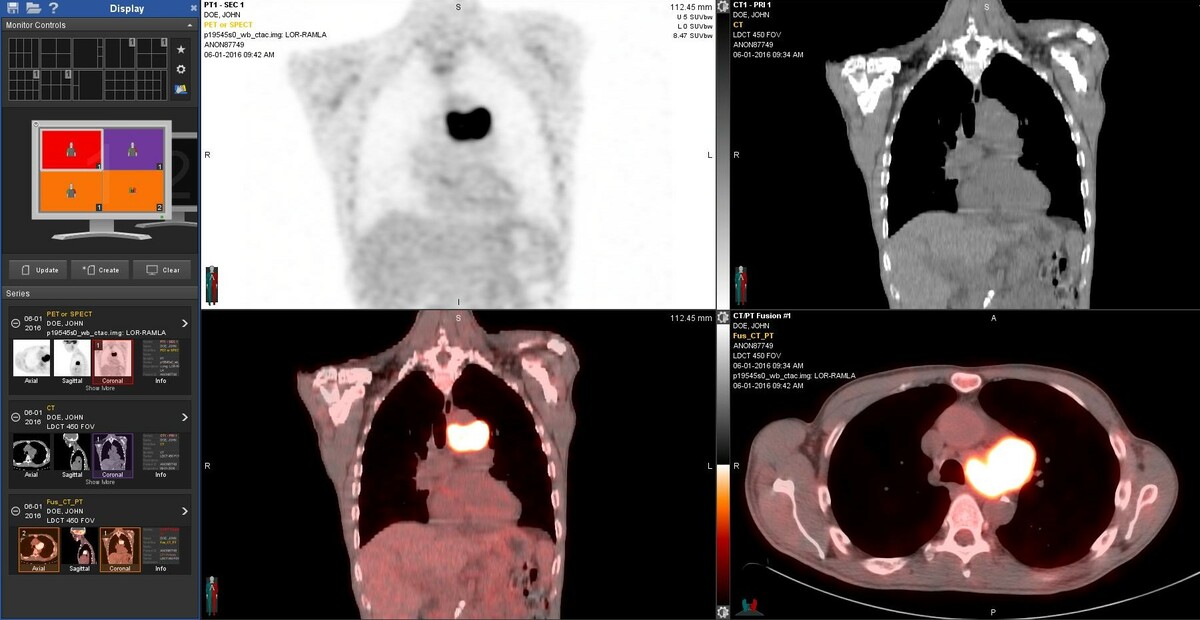

PET is a nuclear medicine technique, which captures images of the human body’s function and reveals information about disease. With PET scan imaging, physicians can collect images of function throughout the entire body, uncovering abnormalities that might otherwise go undetected. No other imaging technique shows the internal metabolism of the body so well. Often times, PET can detect and stage most cancers before they are evident through other tests such as X-ray, MRI, and CT scan. PETalso can give physicians important information about heart viability and neurological disorders, such as Alzheimer’s, seizure disorders and brain tumors.

PET is a reliable, non-invasive way to tell whether or not a tumor is benign or malignant. PET scan imaging evaluates for cancer in a single examination, which allows physicians to stage a cancer and to suggest treatment options earlier, which may spare patients expensive and often painful surgical procedures.

PET Scans collage

How does PET work?

When disease strikes, the metabolism of tissues and cells changes. Using a tracer drug to highlight areas within the body, a PET scan picks up a signal from the organs. If an area in an organ is abnormal, the metabolism will be different than in the surrounding tissues. This data is computer processed and made into images.